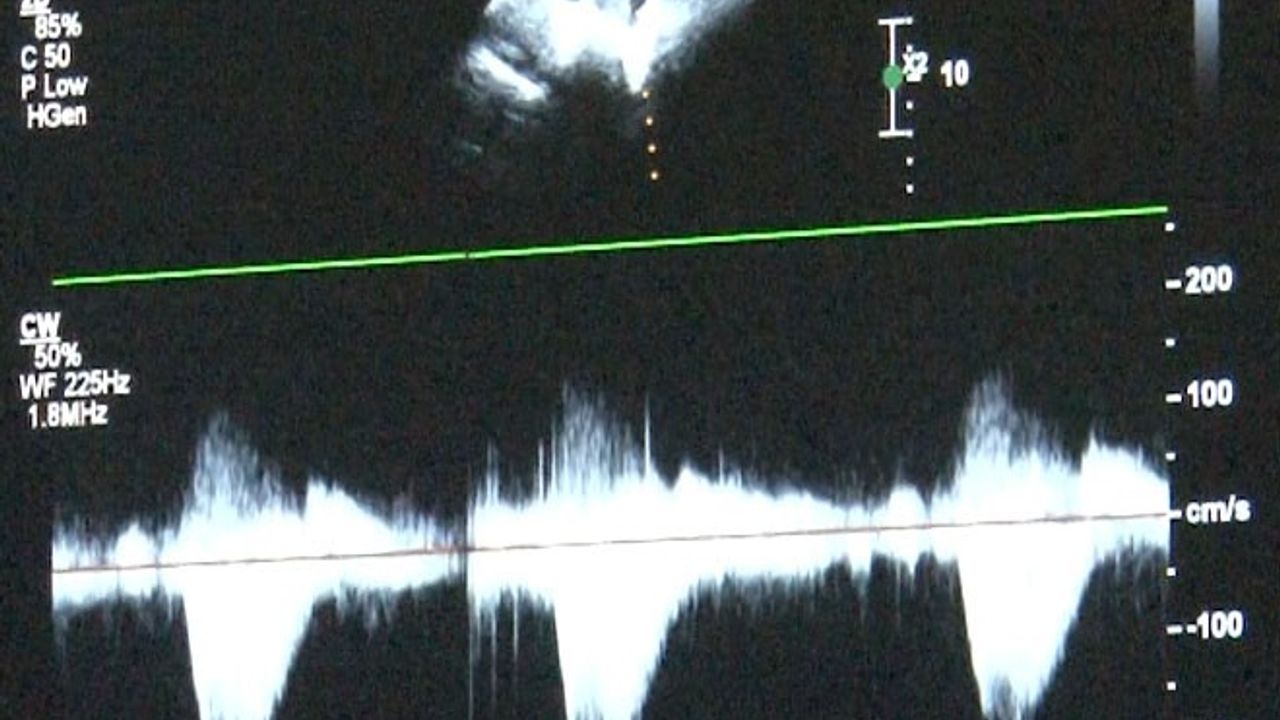

Uzmanlar, erken tanı ve düzenli takiple hayati risklerin önlenebileceğini vurguluyor. Kanuni Sultan Süleyman Eğitim ve Araştırma Hastanesi Çocuk Kardiyoloji Uzmanı Uzm. Dr. Damla Gökçeer Akbulut, doğumsal kalp hastalıklarının çeşitli nedenleri olabileceğini belirterek, “Bazen annenin gebelikte kullandığı ilaçlar ya da diyabet gibi bir hastalığı olması, genetik rahatsızlıklar, bunlar genetik olarak kalp rahatsızlıklarına yol açabiliyor. Bu hastalarda erken tanı mümkün, daha anne karnındayken fetal ekokardiyografi ile doğumsal kalp hastalığı olan bebeklerde doğum sonrası erken müdahale yapabiliyoruz” dedi.

Uzm. Dr. Gökçeer Akbulut, ailelerin özellikle hızlı nefes alıp verme, morarma veya emerken soğuk terleme gibi bulgulara dikkat etmesi gerektiğini ifade ederek, “Doğar doğmaz müdahale edilmediğinde yaşamsal olabilecek sorunlarla karşılaşabiliyoruz, hasta kaybedilebiliyor. Anne karnında olmuyorsa da doğar doğmaz ekokardiyografi yaparak tanısını koymak mümkün” diye konuştu.